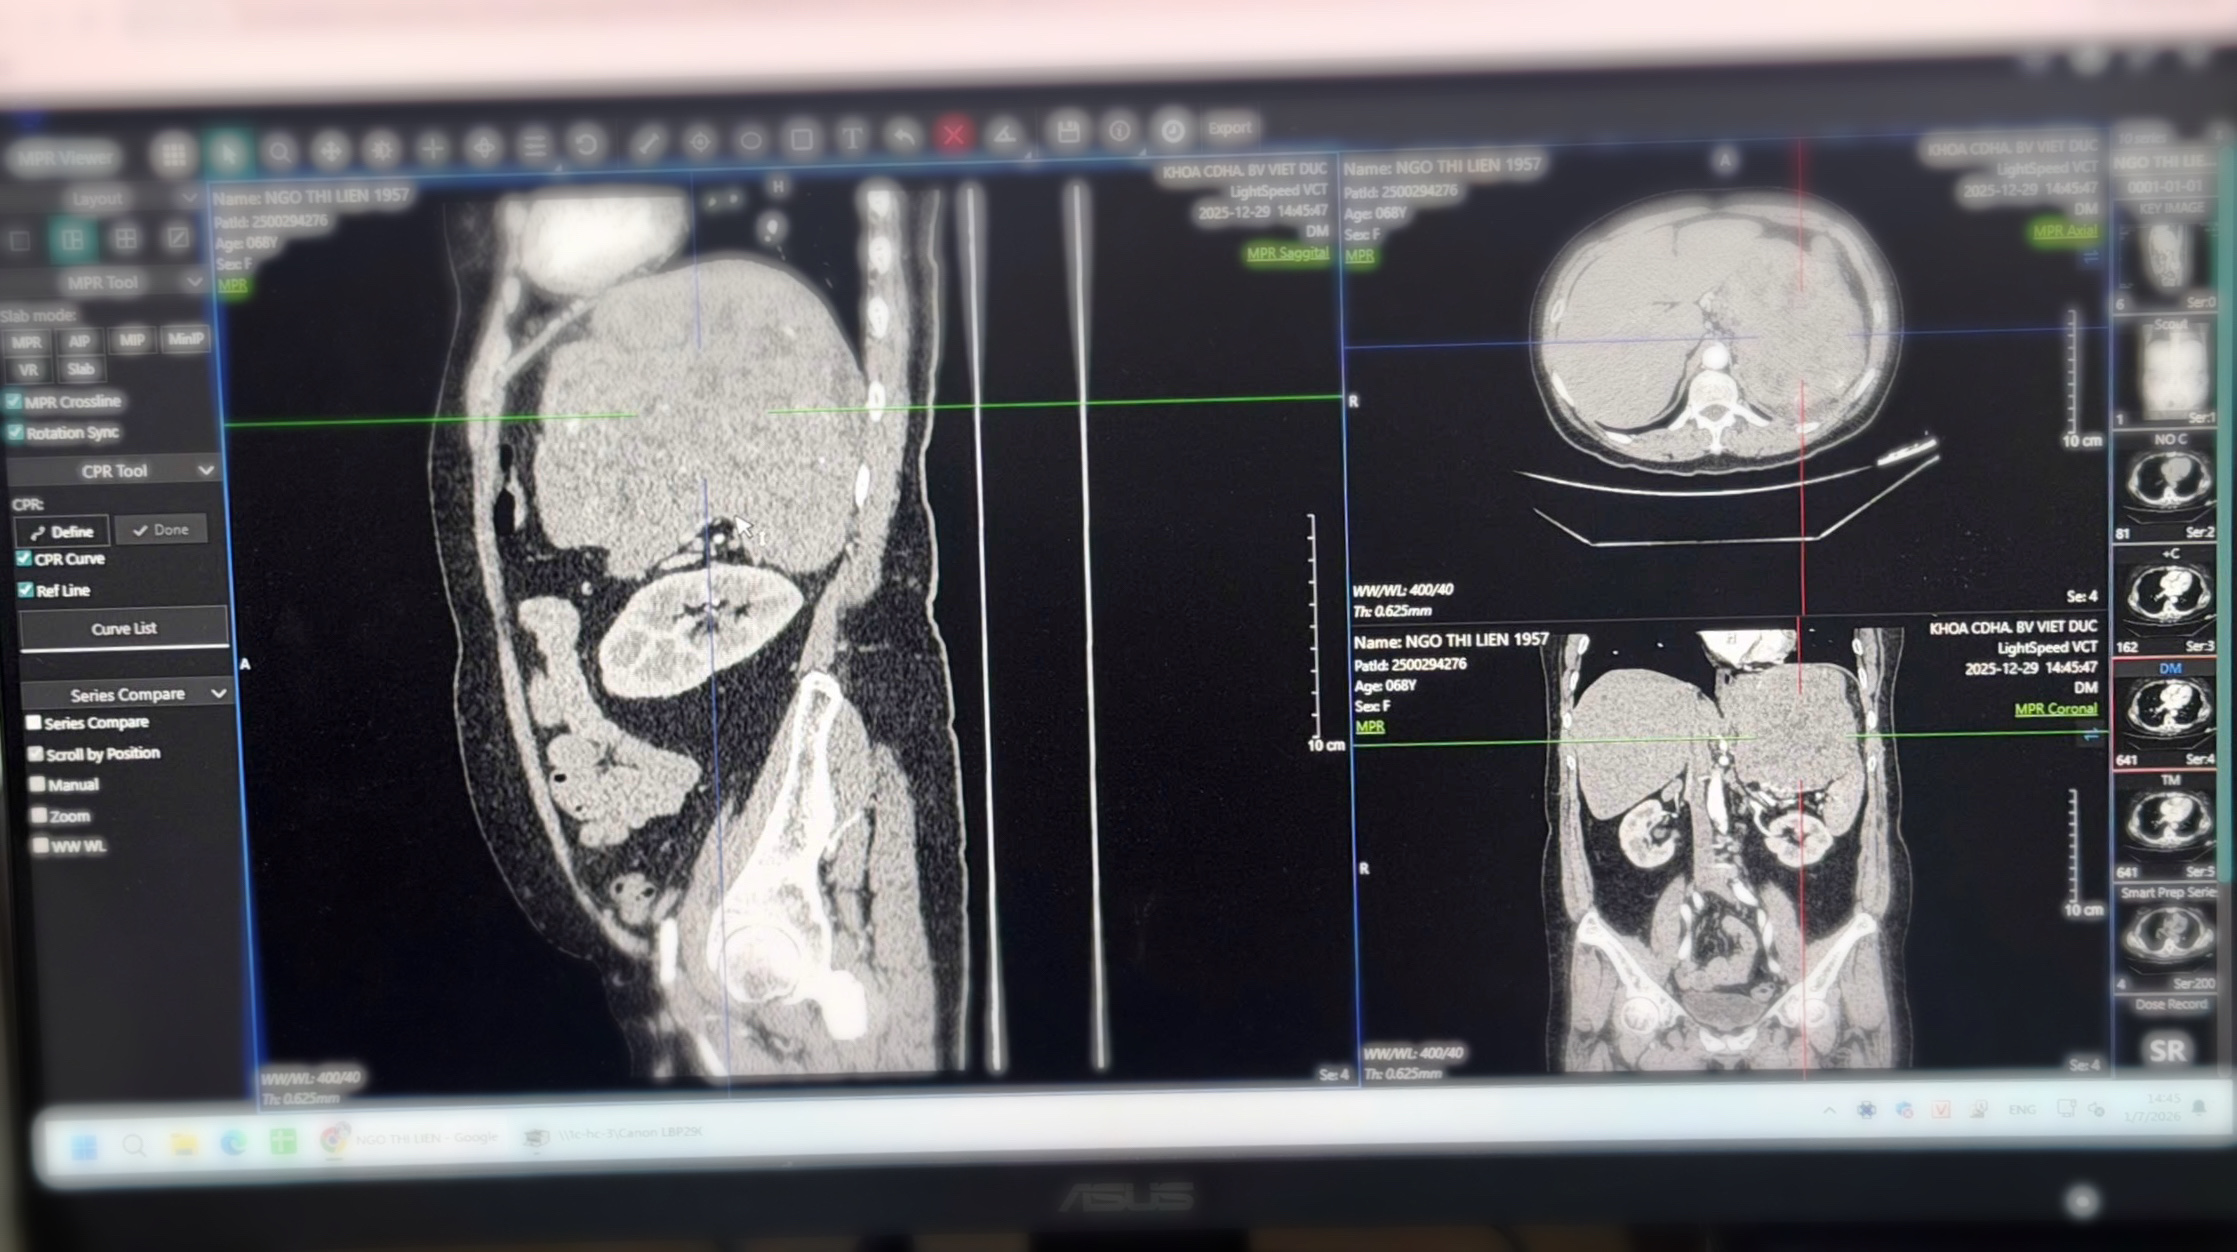

Hình ảnh phim chụp khối u kích thước 20cm của BN

Người bệnh nữ 69 tuổi (Hải Phòng) được chẩn đoán u sau phúc mạc kích thước khoảng 20cm. Trước đó, người bệnh đi khám tại Bệnh viện Đa khoa Hải Phòng và sau đó quyết định chuyển lên Bệnh viện Hữu nghị Việt Đức để được điều trị chuyên sâu.